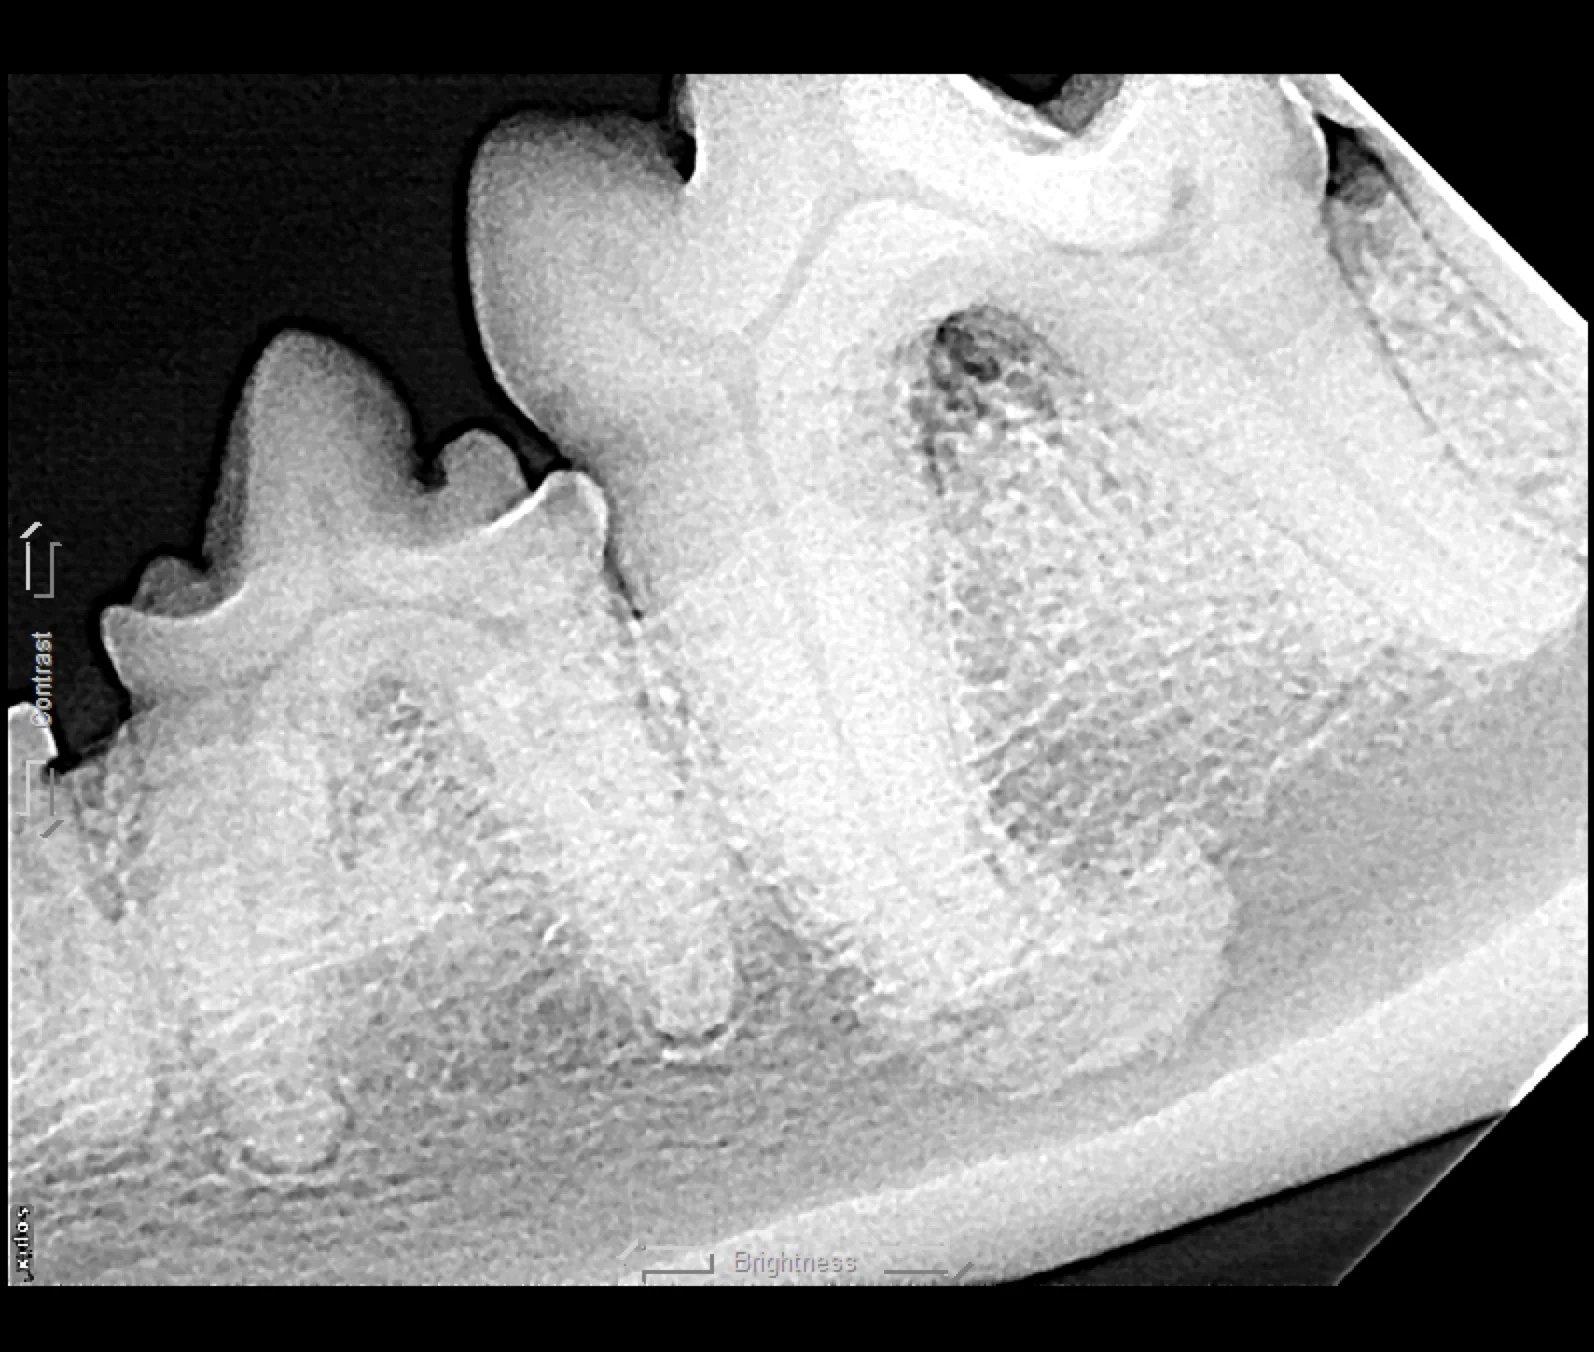

Iatrogenic fracture of the jaw can be a serious complication of surgical extractions and is most commonly associated with surgical extraction of mandibular canine teeth in dogs and cats and mandibular first molar teeth in dogs (Figure 10). These extractions can be difficult to perform, as the root apexes are often located in close proximity to the ventral cortex of the mandible, possibly leading to significant bone loss when severe disease is present and increasing the risk for iatrogenic fracture (Figure 11).

Severe periodontal disease affecting the right mandibular first molar tooth in a dog. Careful extraction technique is necessary to extract the tooth without creating an iatrogenic fracture.

Preoperative intraoral radiographs are critical for assessing fracture risk, especially prior to surgical tooth extraction, and can be used to modify the procedure or refer a patient with high fracture risk to a board-certified veterinary dentist.